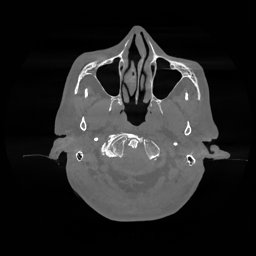

The results for simulated noisy data are shown in Fig. 2. The first and third rows display two representative slices from the test set, and the second and fourth rows present the corresponding error maps. The traditional WCE method suppresses cupping artifacts and recovers some missing anatomical structures but still shows noticeable deviations from the ground truth. Predictions from the four diffusion-based models demonstrate a markedly improved ability to restore anatomical structures. Among them, cDDPM fails to fully reconstruct the patient bed and retains residual noise in its outputs. This noise is attributable to an incomplete reverse denoising process rather than residual Poisson noise, as evidenced in our noise-free experiments (Fig. 5 in the Appendix). PatchDiffusion, diffusionGAN, and I2SB achieve similar visual quality, with I2SB producing the cleanest and most consistent reconstructions.

The experimental results on clinical head data are shown in Fig. 4. The reference images were reconstructed using the fast iterative shrinkage-thresholding algorithm (FISTA) with total variation regularization from non-truncated projection data. In the WCE reconstructions (Fig. 4(b)), severe truncation prevents accurate recovery of anatomical structures outside the FOV. Despite being trained solely on simulated data with a domain gap, all deep learning models can restore a substantial portion of the missing anatomy. Among them, the diffusion-based methods recover soft-tissue boundaries more faithfully than the conventional deep learning approach FBPConvNet, highlighting their stronger image generation capability. However, cDDPM reconstructions exhibit more noticeable noise than those from other methods, consistent with the simulated data results. The patchDiffusion model introduces artifacts within the FOV, likely due to its patch-wise processing strategy. While I2SB shares the same limitations as other diffusion models in perfectly restoring soft-tissue detail, it produces fewer residual noise patterns and fewer artifacts within the FOV boundaries. Overall, Fig. 4 demonstrates the strong efficacy of I2SB in reconstructing real CBCT data.